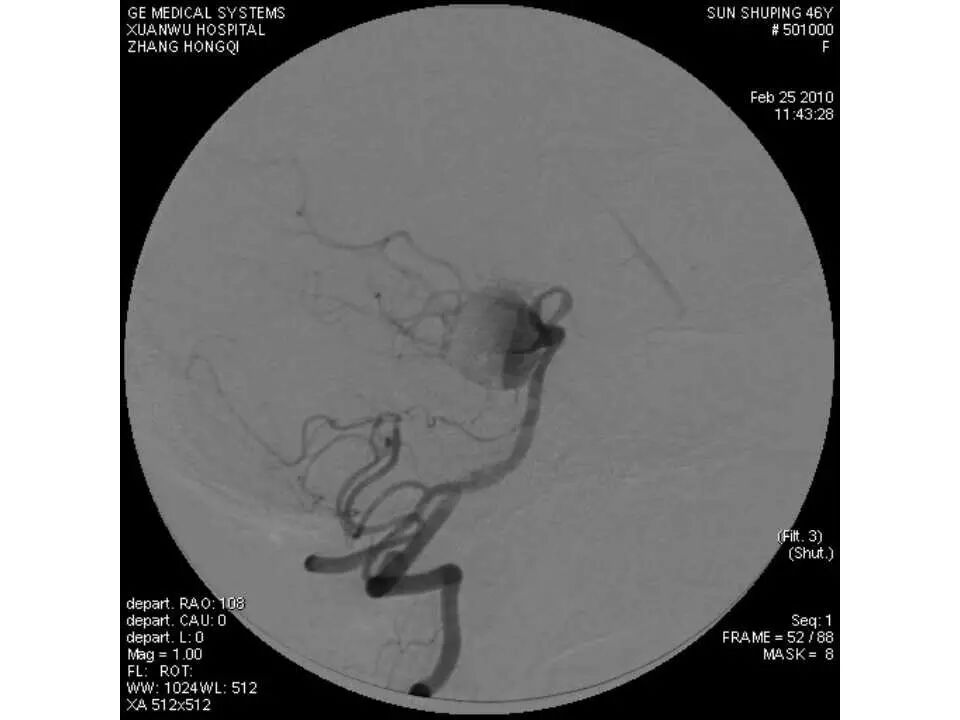

今天为大家分享的是“强生医疗CNV-神经介入专栏”第十五期,由首都医科大学宣武医院何川教授带来的“颅内动脉瘤介入治疗”精彩讲课视频及PPT,欢迎观看、阅读。文章仅代表作者个人观点,如有不同见解,欢迎同道斧正!

何川 ,首都医科大学宣武医院副主任医师,中国医师协会神经介入专业委员会常务委员,长期从事脑血管病和脊髓血管病的手术及介入治疗和相关研究工作。首都医科大学神经外科博士,师从于中国神经介入开创人凌锋教授;日本东北大学医院脑血管病治疗科博士后,师从于日本国脑血管病血管内治疗的开创者高桥教授。